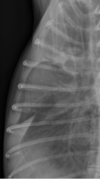

13

Q

pumonary nodules or end on vessel

A